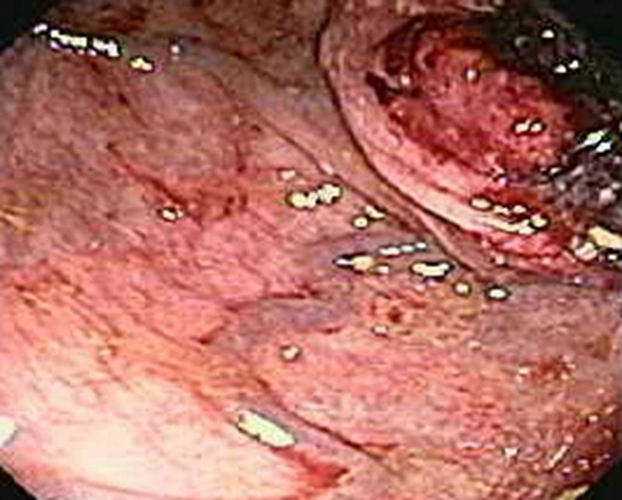

右半結腸癌潰瘍型常見臨床 特點